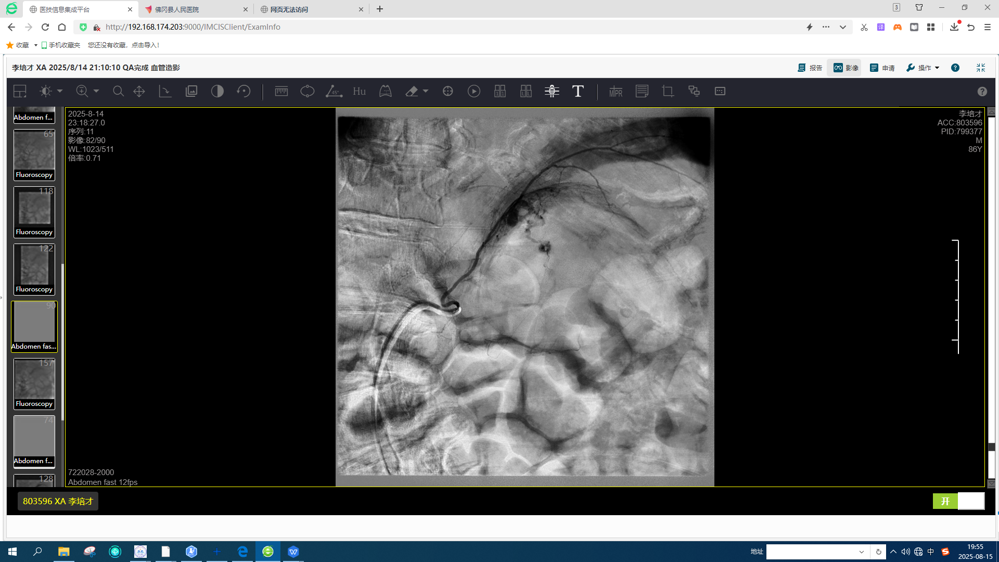

CT增强显示左侧肾上腺肿瘤破裂出血

由于患者高龄,血管迂曲、出血血管隐匿,手术难度大,借助省人医帮扶契机,我院肿瘤科介入团队在省人医微创介入科麦启聪医生的指导下,术中凭借丰富的临床经验及熟练的手术操作,精准定位了肿瘤出血血管,并成功完成了栓塞止血,造影显示肿瘤出血动脉完全封堵,介入术后李伯的生命体征平稳,复查CT未见继续出血表现,复查血常规提示血红蛋白有升高。

术中精准查找出血责任血管

栓塞后造影显示出血动脉成功封堵